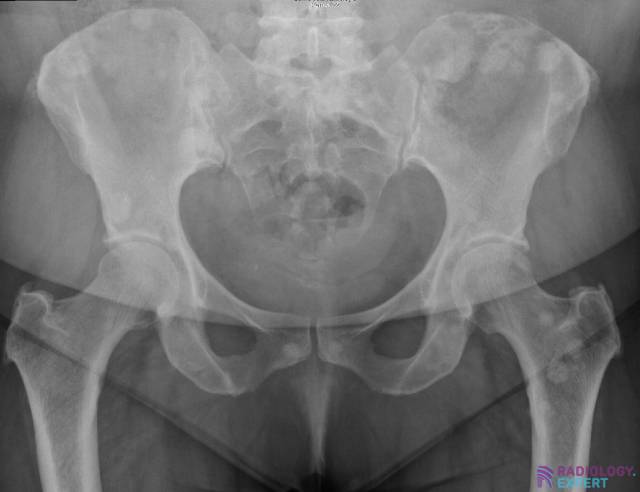

In an older patient (> 40 years old) with multiple osseous lesions, the first diagnosis to consider is bone metastases (fig. 24). A second possible diagnosis is multiple myeloma. Osseous metastases can be lytic, sclerotic (= blastic) or mixed. Many carcinomas of the breast and prostate produce osteoblastic metastases. In contrast, lung carcinomas are often associated with osteolytic metastases.

Figure 24. Multiple sclerotic (= blastic) lesions spread throughout the pelvis and left hip, consistent with bone metastases. The patient is 65 years old with a confirmed diagnosis of breast carcinoma with osseous metastases.